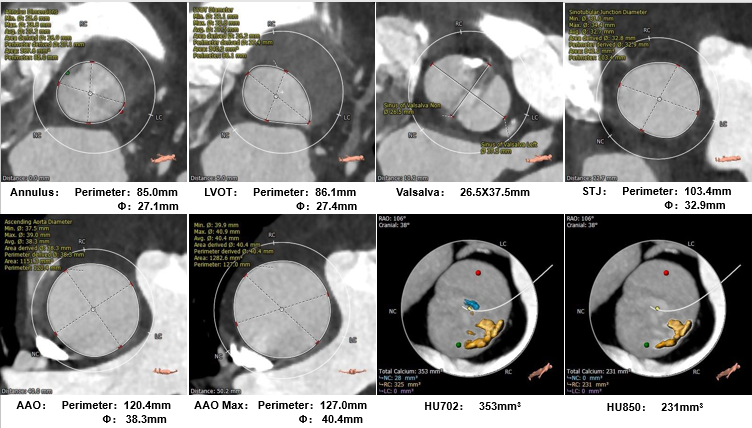

术前CT评估

主动脉根部测量

瓣上测量

患者男,65岁,重度主动脉瓣狭窄诊断明确,符合TAVR手术适应症。通过对CT数据进行分析提示Type0型二叶式主动脉瓣,瓣叶钙化较轻且仅位于右冠窦,瓣膜锚定存在一定困难;经多平面测量分析,瓣环周长径约27mm,瓣上限制较大,左室心肌显著增厚,心腔偏小,存在循环崩溃风险。经王焱教授、王斌教授及吉林大学中日联谊医院TAVR团队对该病例进行全面讨论后,制定22mm球囊预扩,预装AV26瓣膜的手术策略;术中在瓣膜完全释放后出现血压下降,TAVR团队沉稳处理,排除心包积液、主动脉瓣大量反流等因素后,给予0.9%NaCl静脉推注+静脉滴注、多巴胺静脉泵入等对症治疗后血压逐渐恢复并持续稳定,术后超声评估各项参数满意,效果显著,为患者带来极大获益。